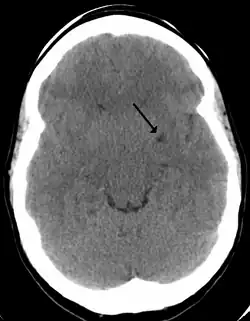

Dilated perivascular spaces are categorized into three types:[7]

- Type 1 are located on the lenticulostriate arteries projecting into the basal ganglia

- Type 2 are located in the cortex following the path of the medullary arteries

- Type 3 are located in the midbrain

Clinical significance

The clinical significance of perivascular spaces comes primarily from their tendency to dilate. The importance of dilation is hypothesized to be based on changes in shape rather than size.[13] Enlarged spaces have been observed most commonly in the basal ganglia, specifically on the lenticulostriate arteries. They have also been observed along the paramedial mesencephalothalamic artery and the substantia nigra in the mesencephalon, the brain region below the insula, the dentate nucleus in the cerebellum, and the corpus callosum, as well as the brain region directly above it, the cingulate gyrus.[5] Upon the clinical application of MRI, it was shown in several studies that perivascular space dilation and lacunar strokes are the most commonly observed histological correlates of signaling abnormalities.[13]